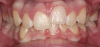

Canine substitution can be an excellent alternative for the replacement of the missing maxillary lateral incisor (Figure 1 and Figure 2). This treatment option can be particularly effective if the canine has a flat facial surface, is not too wide mesiodistally, and has a color similar to the contralateral lateral incisor. Patients with missing lateral incisors who present with maxillary dentoalveolar protrusion and/or an Angle class II molar relationship and minimal crowding in the mandibular arch are considered excellent candidates for canine substitution.7

Fig 1. Patient was missing teeth Nos. 7 and 10 (Fig 1). Canine substitution was the treatment used to replace these missing teeth (Fig 2).

Fig 2. Patient was missing teeth Nos. 7 and 10 (Fig 1). Canine substitution was the treatment used to replace these missing teeth (Fig 2).